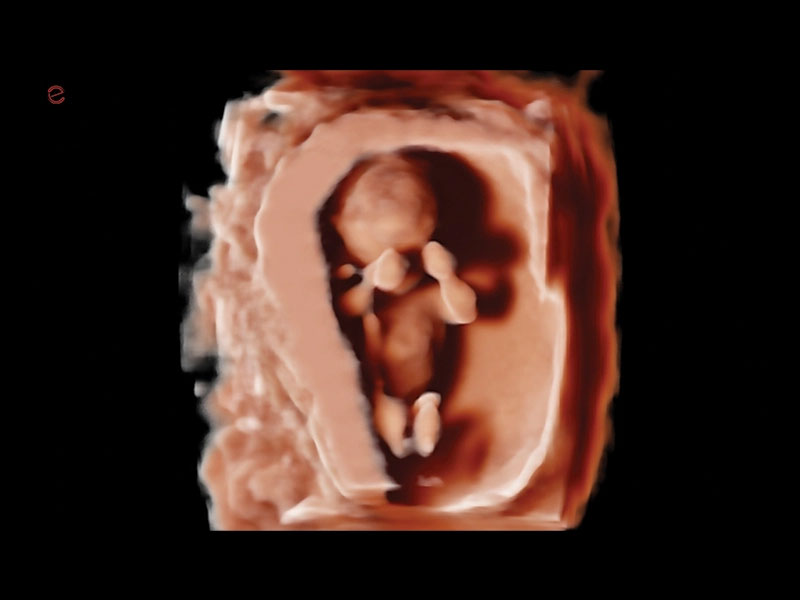

Med sine avancerede funktioner og høje billedkvalitet er MyLab™A70 ideel til et bredt spektrum af anvendelsesområder, fra akutte traumer til komplekse vurderinger. Den intuitive brugerflade gør betjeningen enkel, og de AI-drevne værktøjer hjælper med scanningsarbejdet og lader dig fokusere på patienten.

De indbyggede AI-værktøjer hjælper med automatisk billedoptimering og arbejdsflow, fx eScan, Autoscan og eDoppler. Derudover understøtter A70 avancerede målinger som strain-analyse og lever-elastografi.